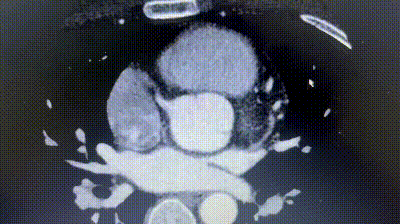

2 La ATC coronaria reveló un origen anómalo de la arteria circunfleja izquierda (LCX) del seno coronario derecho, con un curso entre la aorta y la aurícula izquierda.

La distancia entre el ASD y el LCX aberrante fue de sólo 6mm.